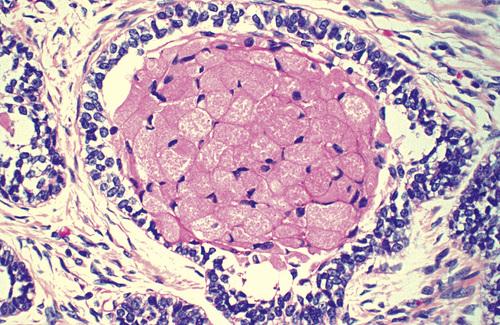

A dentigerous cyst from a 53-year-old man showing islands of invasive epithelial cells in the cyst wall.

odontogenic carcinoma